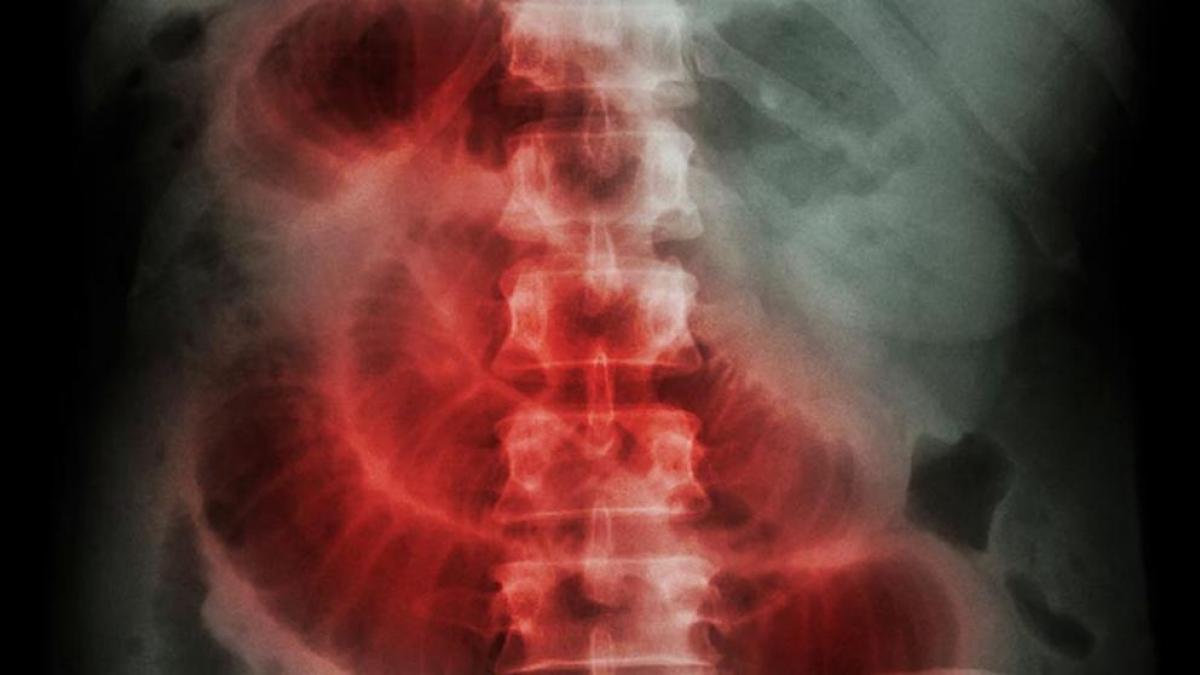

Manejo quirúrgico versus no quirúrgico para pacientes con obstrucción intestinal maligna

02 agosto 2023

En pacientes con obstrucción del intestino delgado por enfermedad maligna intraabdominal o retroperitoneal se comparó un enfoque de tratamiento quirúrgico con uno no quirúrgico, observando que no modificó la evolución clínica durante los tres meses siguientes. Estos hallazgos deben informar las decisiones de tratamiento para pacientes hospitalizados con obstrucción intestinal maligna. The Lancet Gastroenterology & Hepatology, 1º de agosto de 2023.